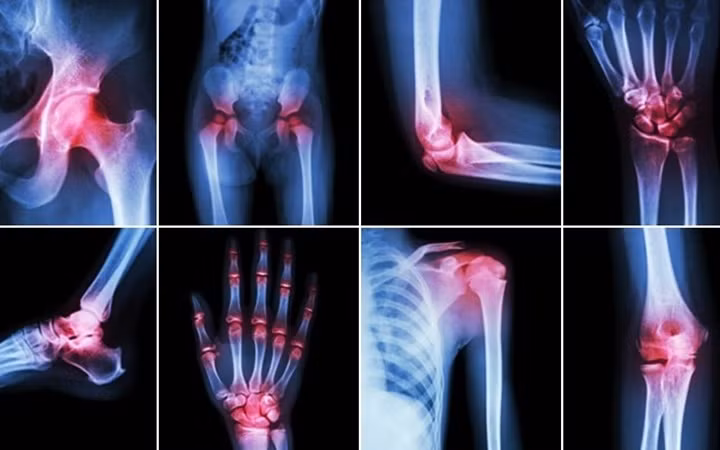

![]() |

| Viêm khớp: Mùa Đông cũng là khắc tinh của những người bị đau khớp. Những người bị viêm khớp cho biết, các khớp xương của họ cứng hơn và bị đau hơn vào mùa Đông. Tuy nhiên, không có cơ sở nào chứng minh rằng thời tiết lạnh hơn sẽ gây ra bệnh đau khớp. Một số chuyên gia cho rằng, con người bị trầm cảm hơn trong thời tiết mùa Đông, khiến họ cảm nhận nỗi đau sâu sắc hơn. Các chuyên gia đưa ra lời khuyên rằng, việc tập thể dục hàng ngày có thể giúp cải thiện thể chất và cả tinh thần của người bệnh. Bơi lội là môn thể thao lý tưởng cho những người có vấn đề về khớp. Ảnh: KT |